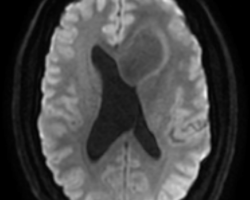

- IRM : coupes axiales, séquences en diffusion B1000, perfusion, T1 et T2 : tumeur hypoT1, hyperT2, peu de diffusion = peu d’œdème, localisation plutôt frontale. Pas de prise de contraste (pas de cliché ici = à compléter) Compte tenu de l’âge, évocateur d’un gliome bas grade. De ce fait, rechercher une comitialité avant tout geste chirurgical.

IRM : lésion basifrontale gauche développée aux dépens du gyrus rectus qui remonte vers l’hypothalamus comprimant les foramens de Monro induisant une probable hydrocéphalie obstructive. Pas de prise de contraste mais séquences en perfusion non exploitables.